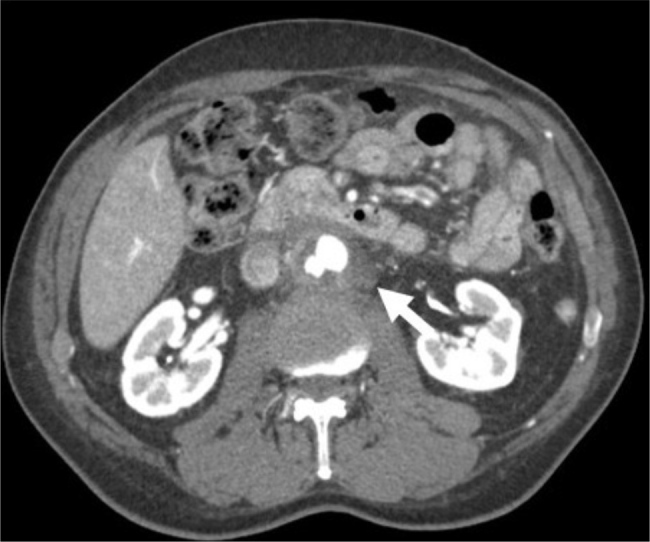

Case description: We report the case of a 70-year-old man presenting with flank pain and periaortitis, in whom positron emission tomography/computed tomography (PET/CT) scan revealed moderate-to-severe 18F-fluorodeoxyglucose (FDG) uptake. Despite negative cultures, a Karius test and urine antigen confirmed Streptococcus pneumoniae as the causative agent. The patient underwent successful open surgical repair of a mycotic pararenal abdominal aortic aneurysm, followed by targeted antibiotic therapy.

Discussion: Pneumococcal periaortitis is a rare condition with few reported cases, though S. pneumoniae has been implicated in various vascular infections including mycotic aneurysms, and diagnostic challenges persist, especially when blood cultures are negative. The Karius Spectrum, despite its cost and limited guidance for use, and FDG-PET/CT imaging have emerged as helpful tools in identifying infectious aetiologies, with high maximum standardized uptake value values favouring infection over autoimmune causes, as seen in this case.

Conclusion: Infectious periaortitis should be suspected when there is a high uptake of FDG on PET/CT prompting an infectious disease work-up which may include a Karius test.